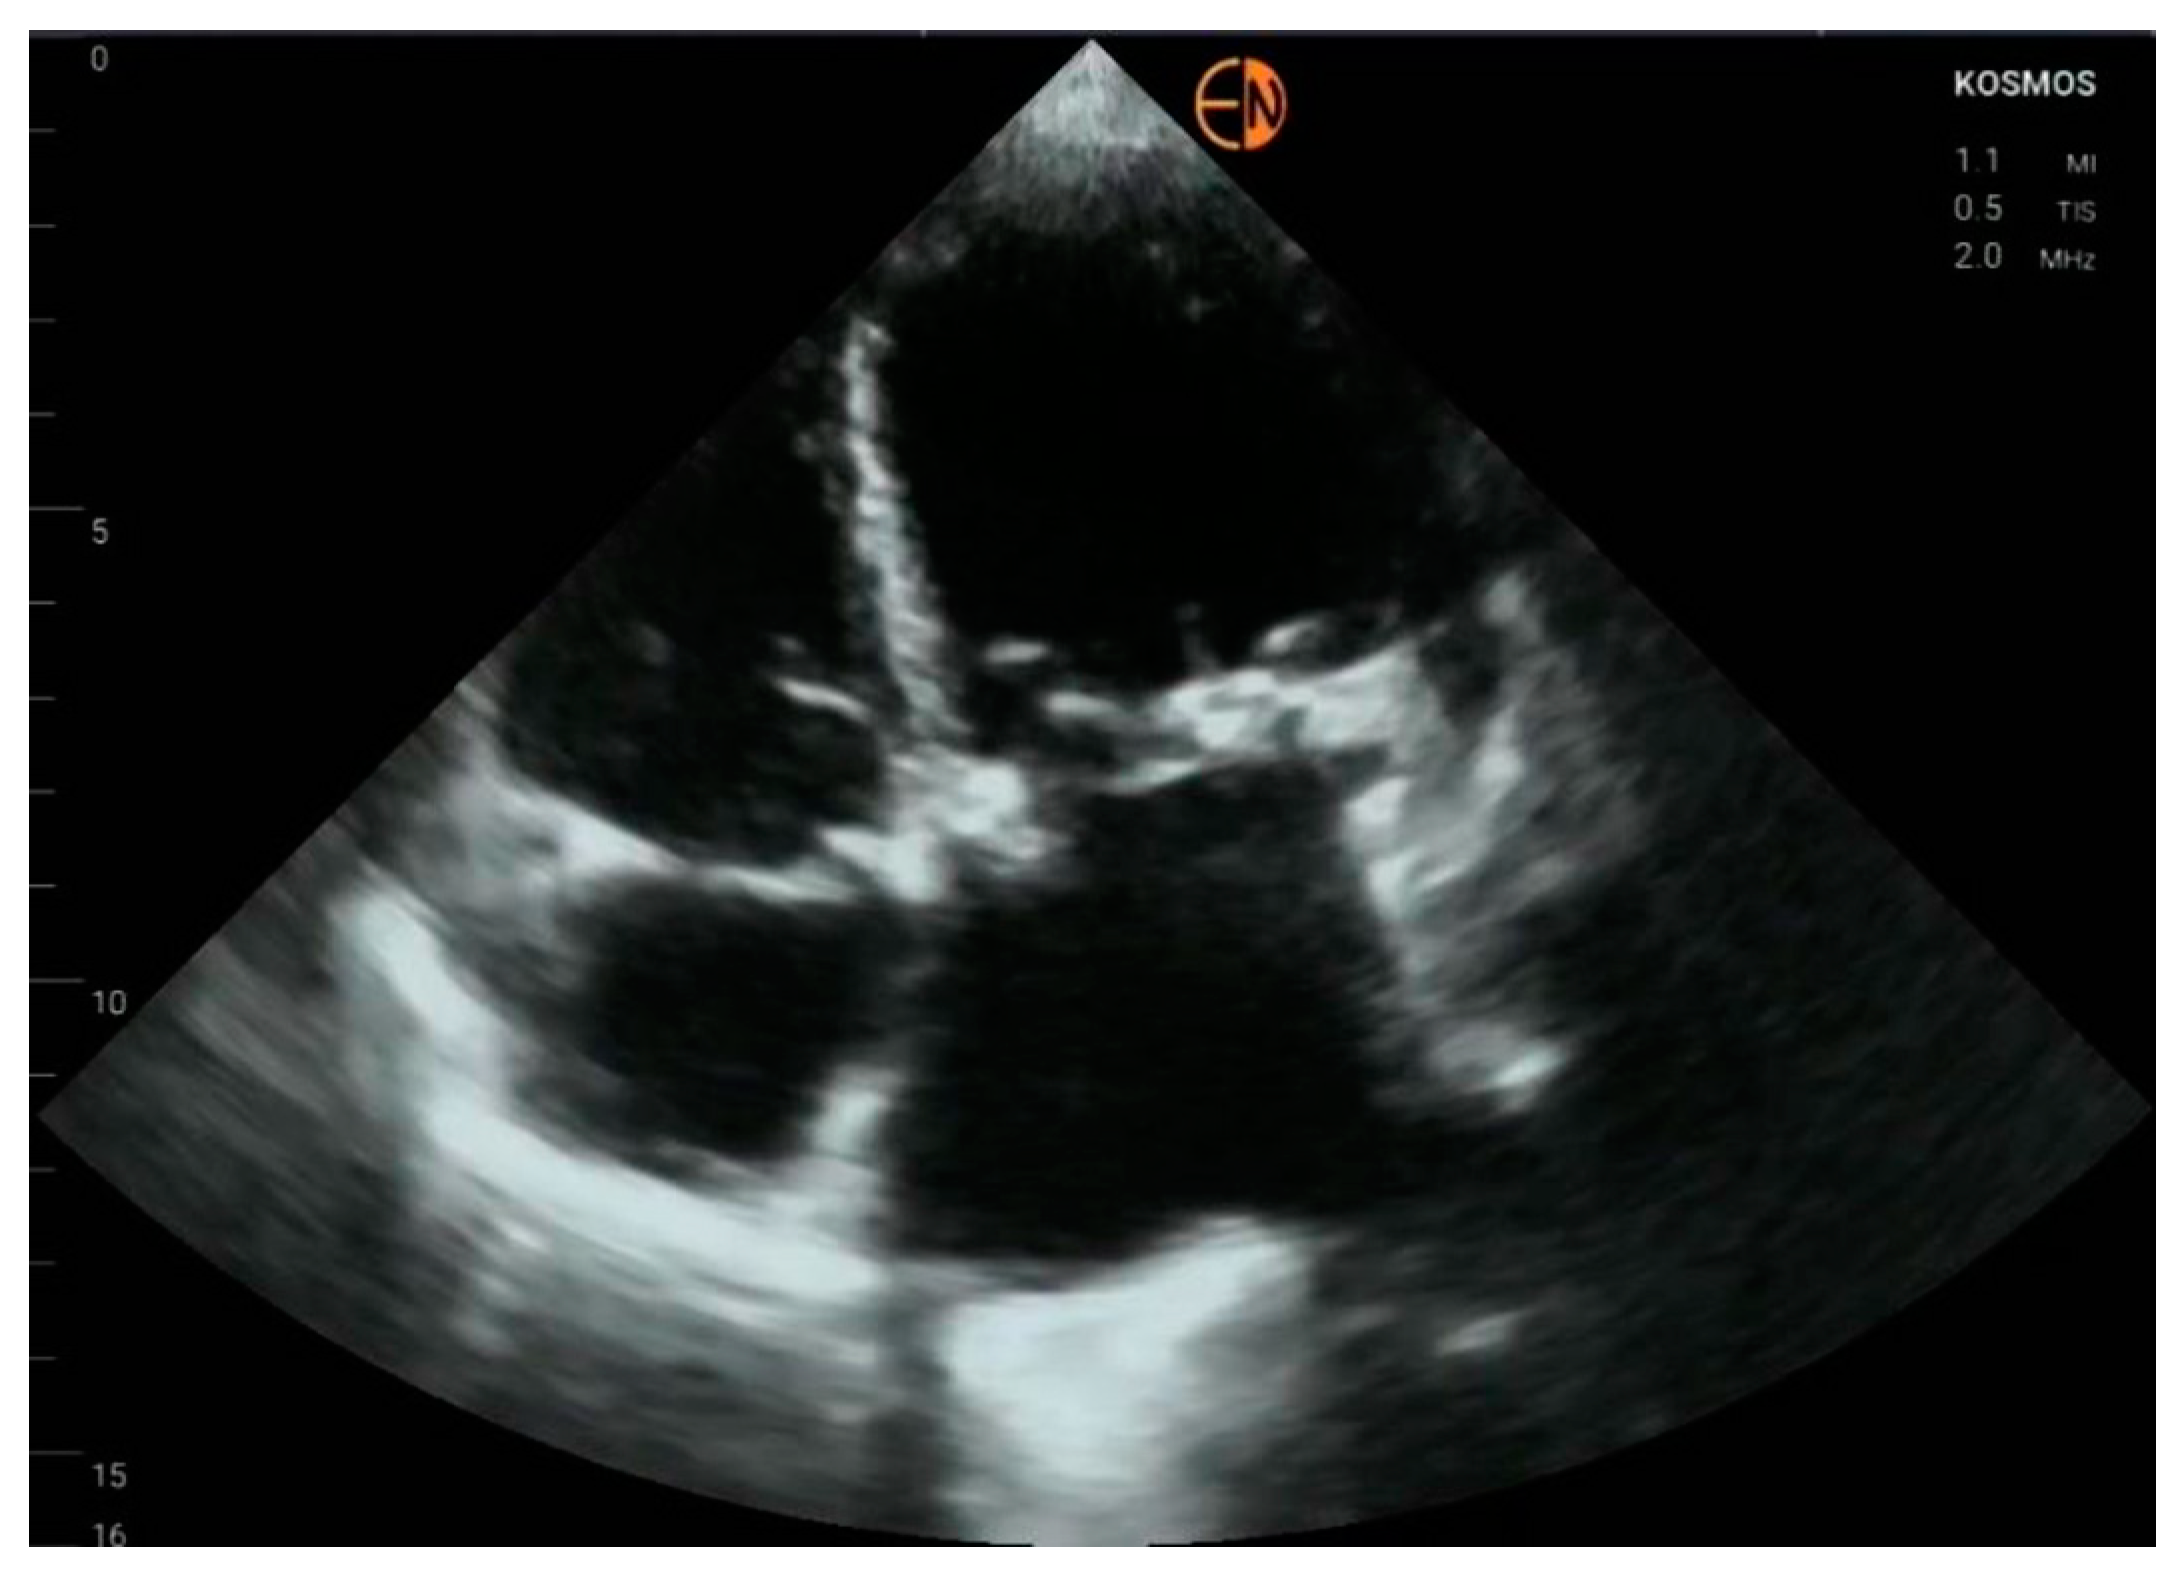

3.2. Measurements of Cardiovascular Structures

3.3. Valvular Stenosis and Regurgitation